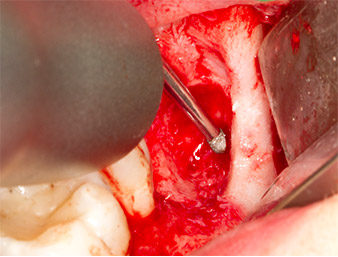

Nach Leitungs- und Lokalanästhesie wurde das Operationsfeld für einen bukkal-retromolaren Zugang weichgewebig eröffnet und dargestellt (Abb. 3).

Das Gewebe über dem Wurzelrest war nicht vollständig verknöchert und bestand zu einem großen Teil aus entzündlich verändertem Granulationsgewebe (Abb. 4).